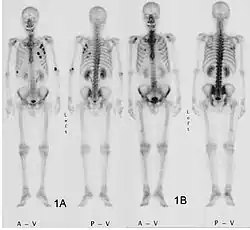

- Aufnahmen pathologischer Frakturen

-

Pathologische Fraktur des Oberarmknochens bei einer Metastase eines Nierenzellkarzinoms -

Pathologische Fraktur des linken Oberarms bei Knochenmetastase einer Patientin mit Brustkrebs -

Ganzkörperknochenszintigramm mit 99mTc-HDP der Patientin mit der Oberarmfraktur aufgrund einer Brustkrebsmetastase